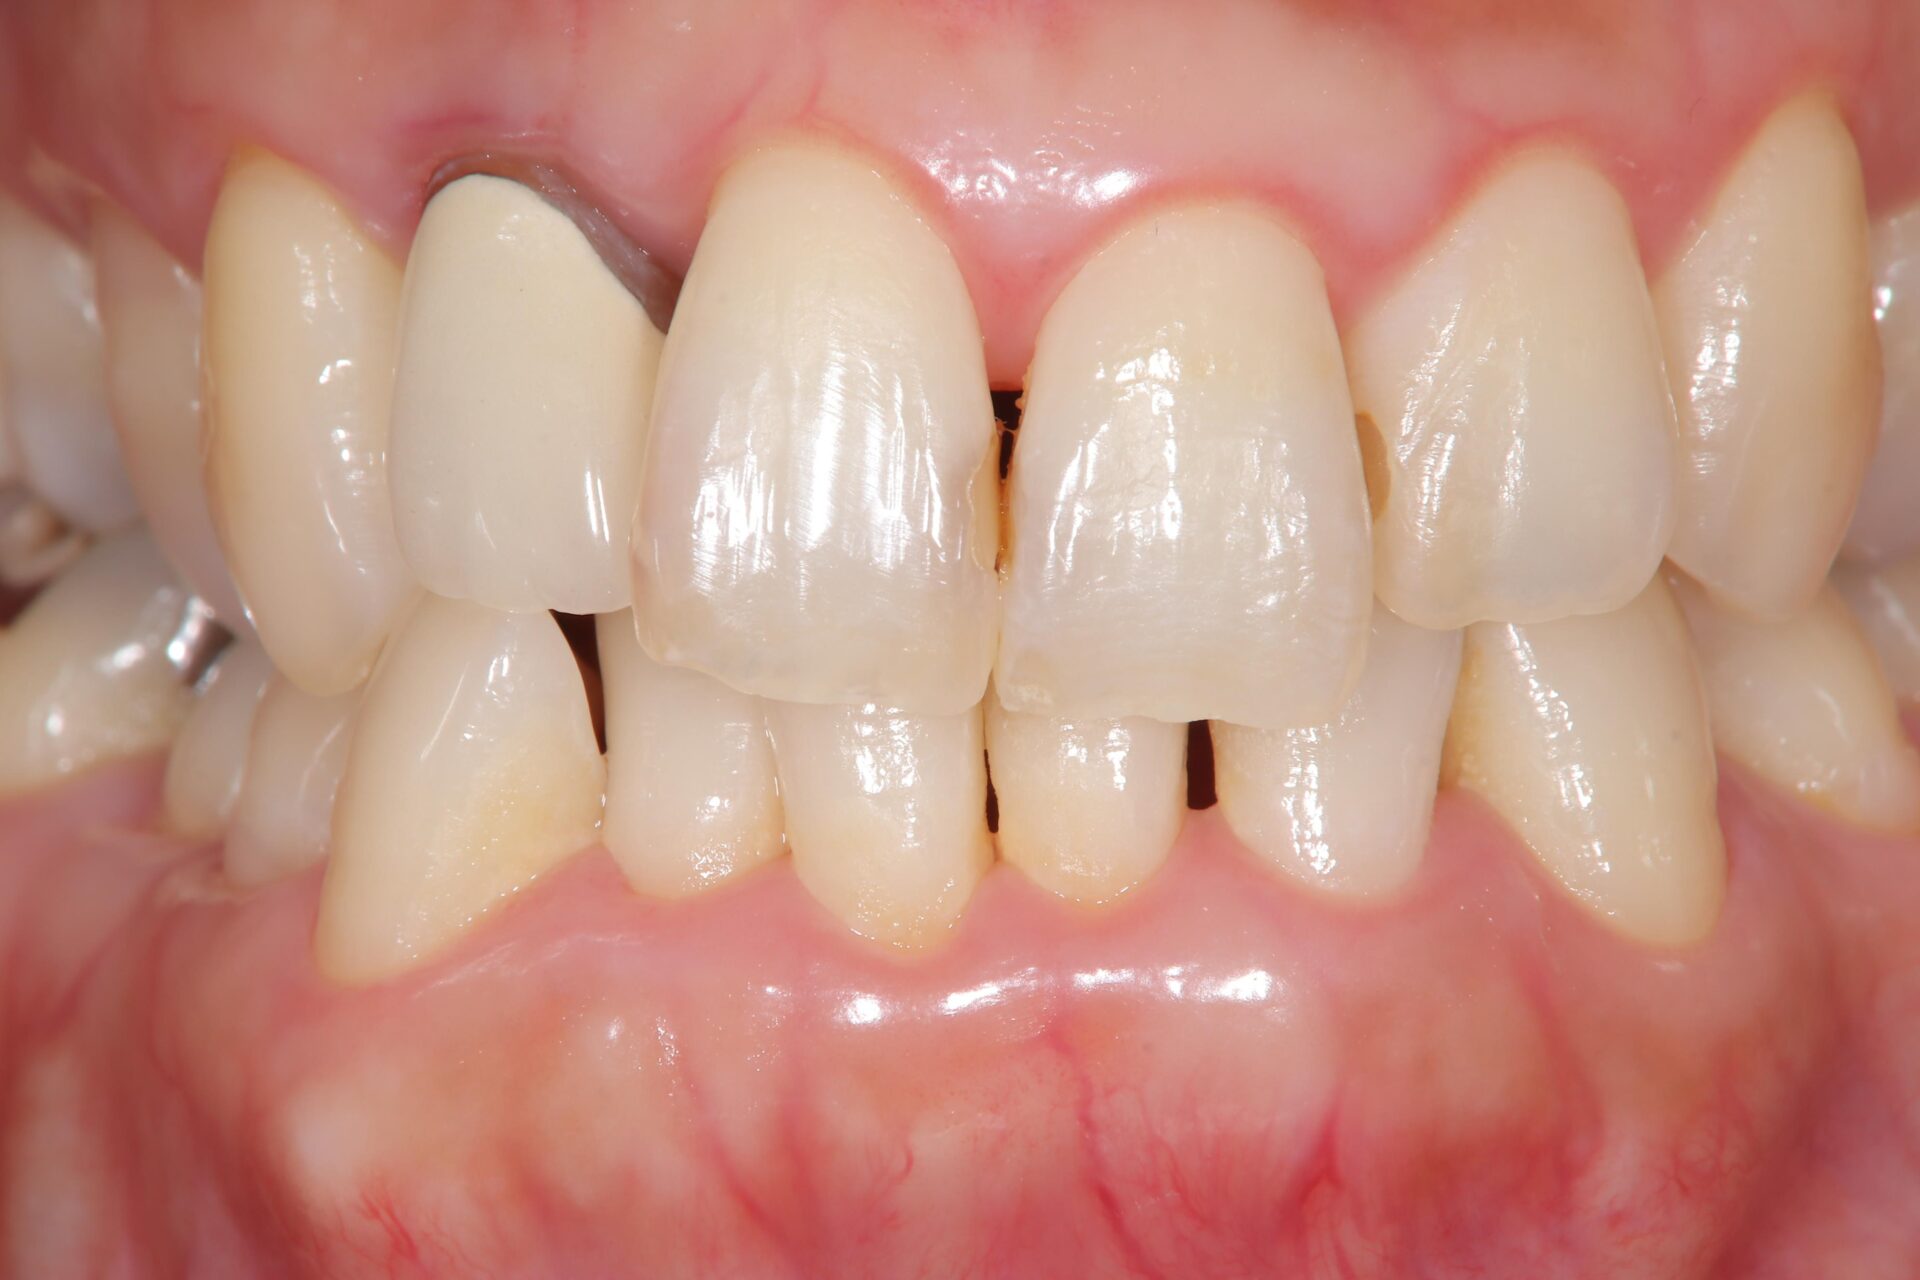

2023.1/25 他院で被せ物を作成した歯が腫れて痛みがあるということでご来院。

2024.6/5 被せ物は外し、当院で改めて根っこの治療を行いました。

2024.9/5 右上2番の治療が終わり、ジルコニアクラウンの被せ物を作成しました。

治療部位 | 右上2番 |

費用 | 保険分+自費で約11万円 |

治療期間 | 21ヶ月 |

注意事項(リスク・副作用など) | 治療の刺激や薬剤の刺激により、治療後数時間から数日後に痛みや腫れが生じる場合があります。 |

カテゴリ | 歯内療法 |